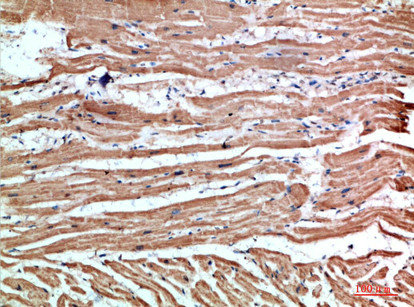

Immunohistochemical analysis of paraffin-embedded human-heart, antibody was diluted at 1:200